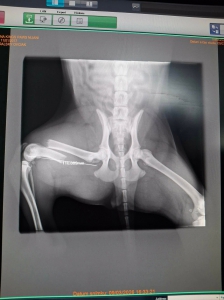

Včera sme prijali toto zranené šteniatko. Fenka zostala na pozorovanie na veterine a zistili že má zlomenú stehennú kosť :(

DOLORES má po operácii ♥. Ďakujeme všetkým za pomoc ♥♥♥. Držte malej palce aby bola čoskoro fit :)

Dolores po operácii pozdravuje. Zotavuje sa výborne a rýchlejšie ako sme mysleli ♥♥♥